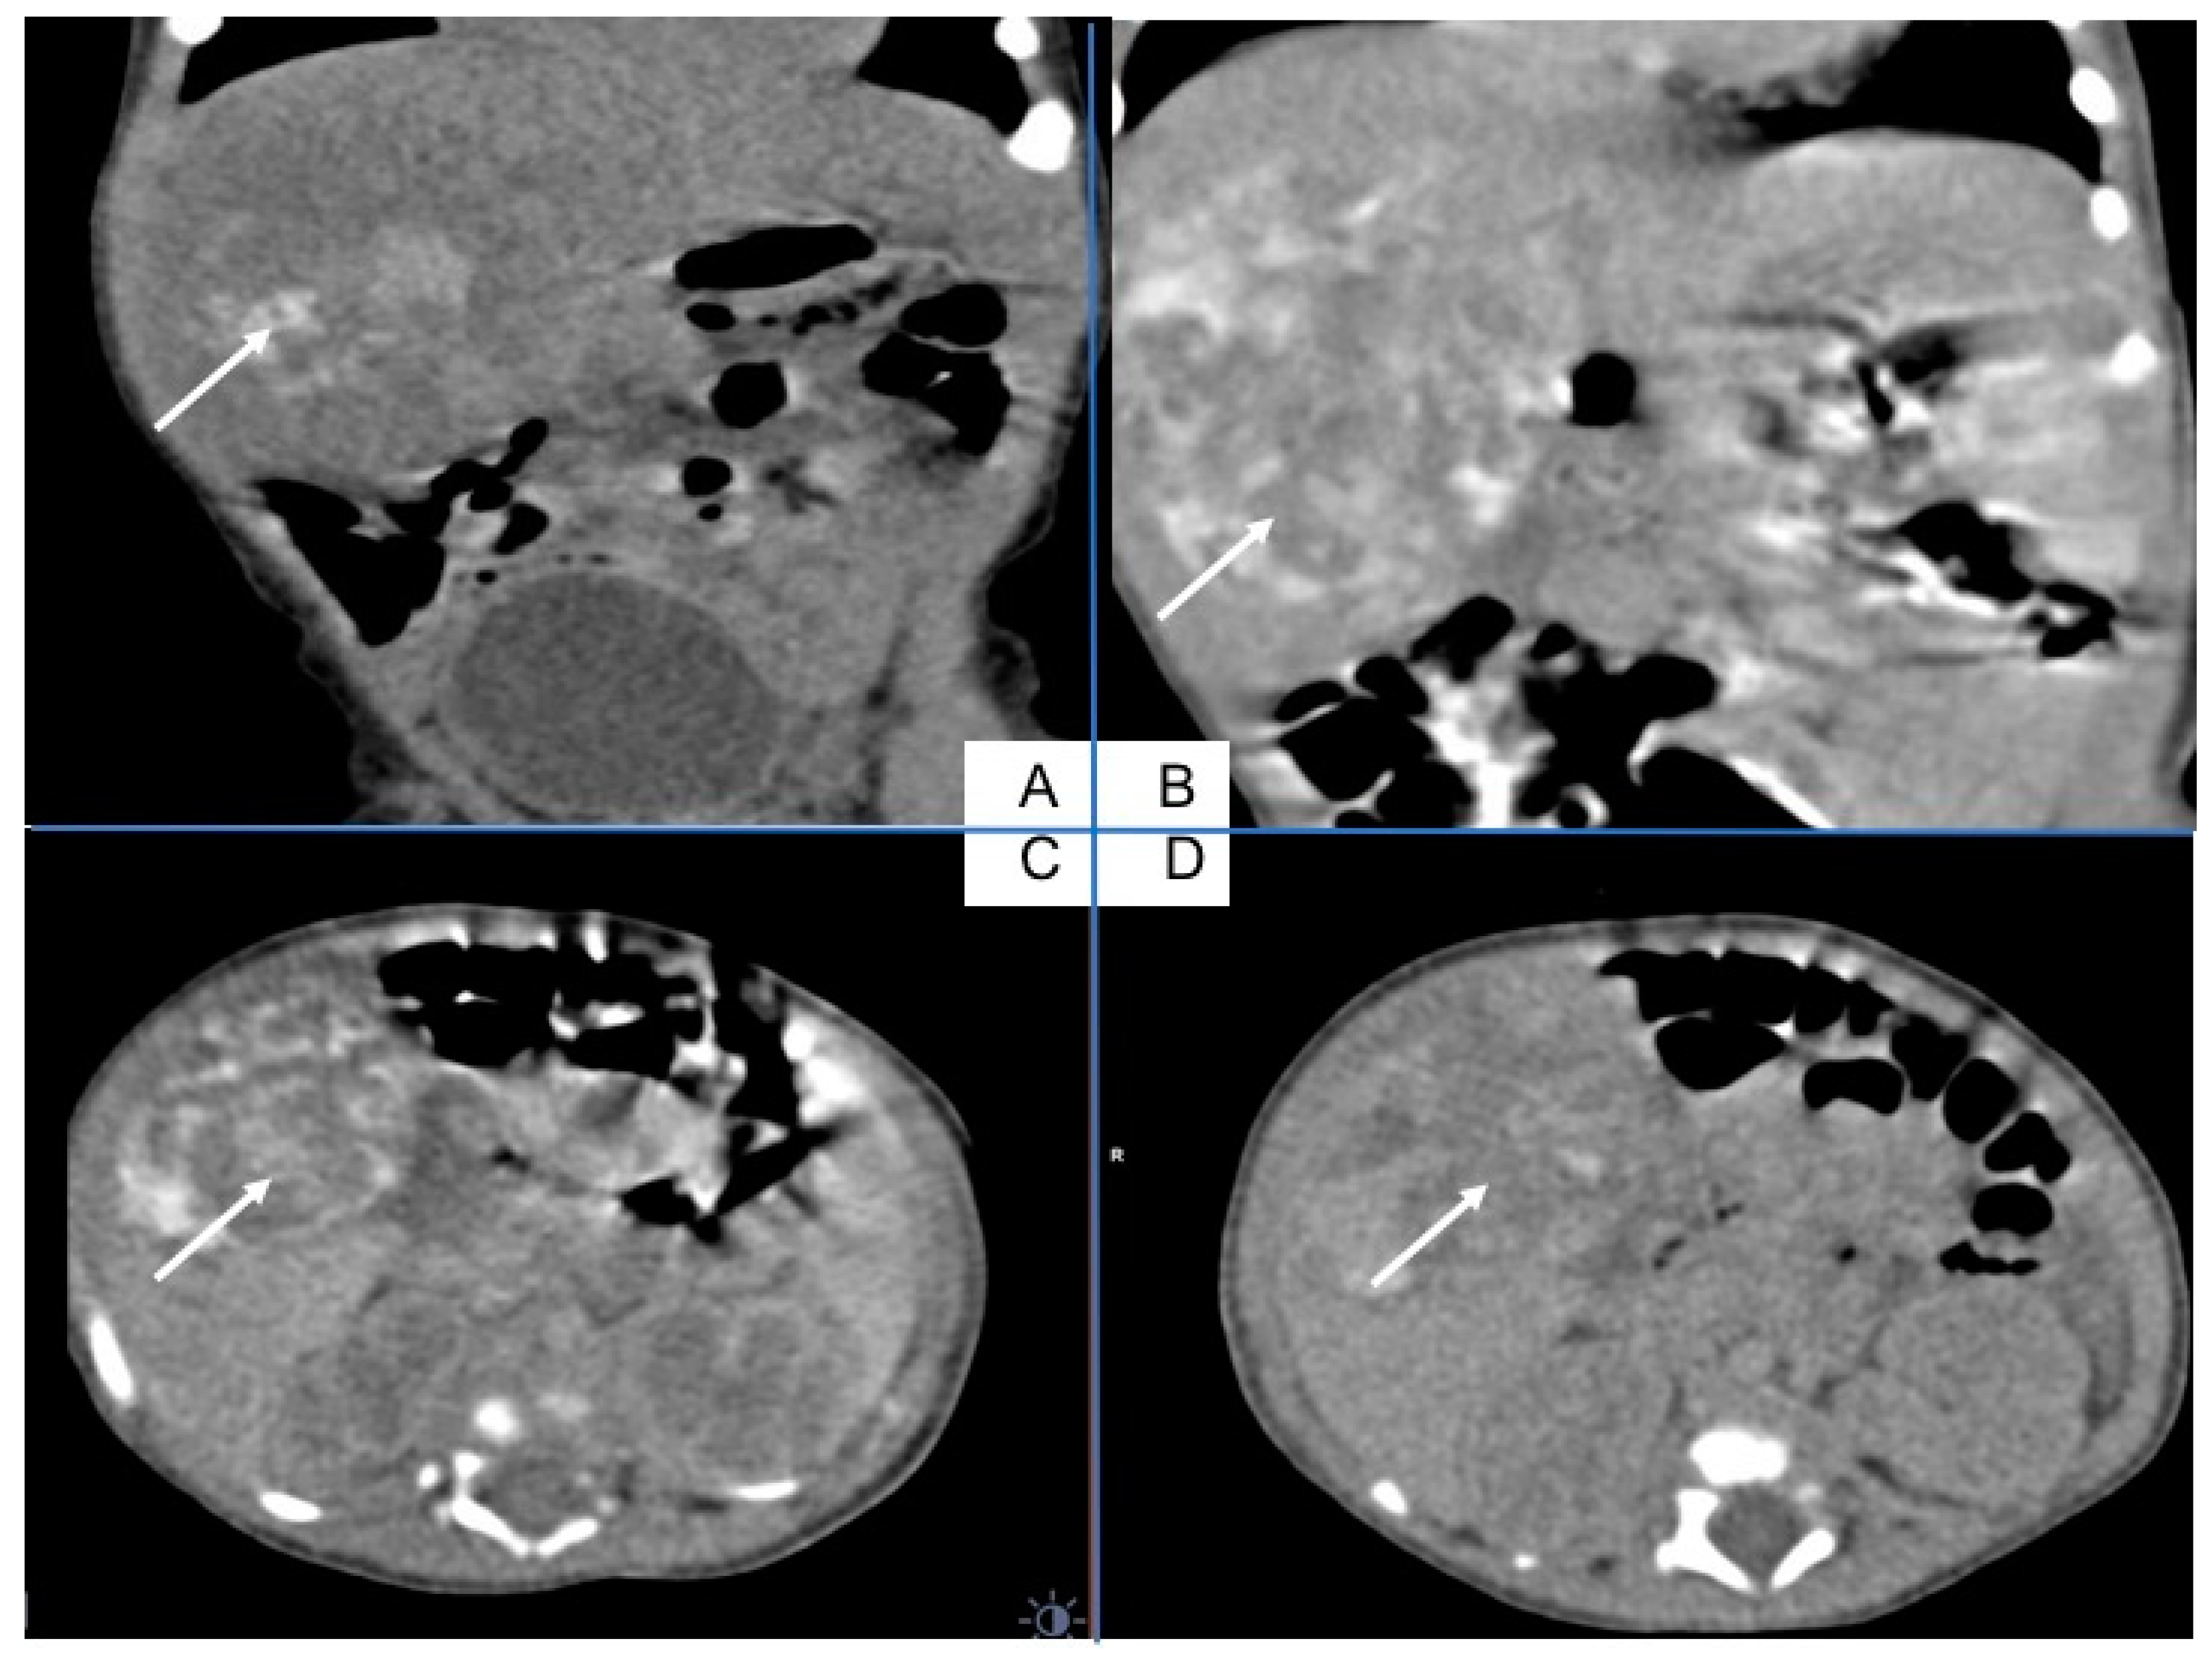

The ultrasound examination performed on admission in the oncological ward showed a massive hypodensive lesion in the right lobe of the liver, which was 5 cm in diameter. The lung X-ray indicated three circular metastatic lesions. Chest and abdominal computed tomography (CT) showed numerous (about 50) metastatic lesions in both lungs, and a liver tumor 5.2 cm × 3.7 cm × 4.8 cm in the right lobe. Lung window axial CT image shows multiple pulmonary rounded nodules of variable size, scattered throughout both lungs (Figure 1).

Figure 1. Chest CT with numerous metastatic lesions in both lungs.